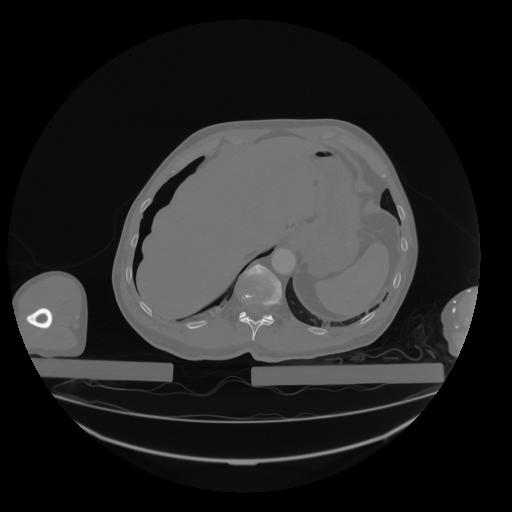

28 CUERPO,CE,Vol,2.0,CUERPO,,